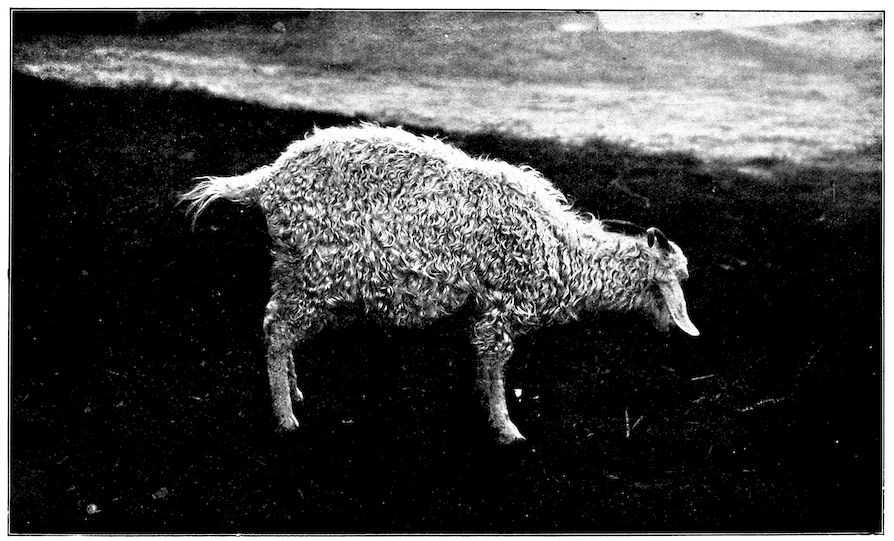

Fig. 1.—Rachitis in a young goat.

Fig. 1.—Rachitis in a young goat.